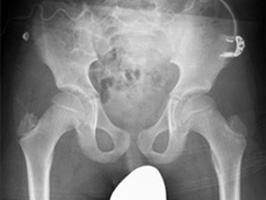

Innovative image enhancement technology designed to increase the clarity of adult erect chest radiographs by suppressing bones on digital images.